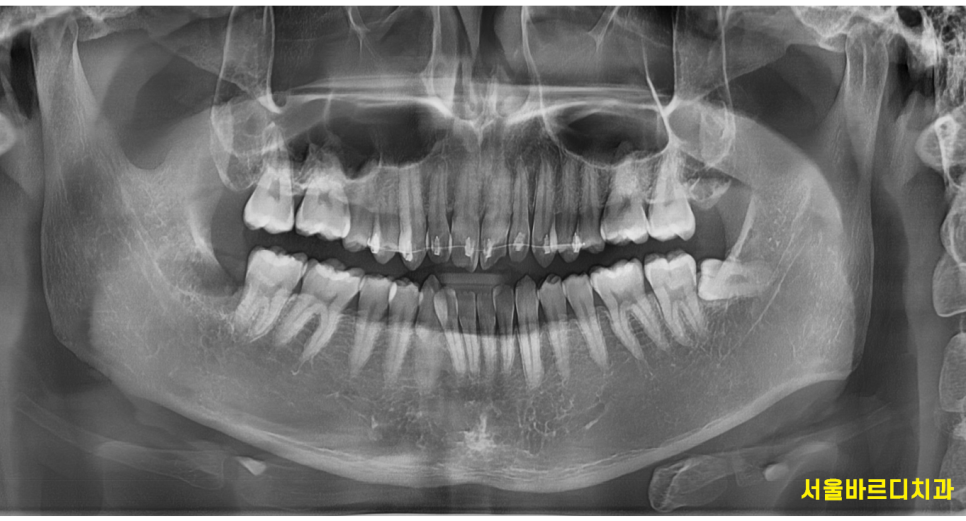

치아 상태, 골격 구조, 나이 , 생활 습관 등 말이죠!

치과에서 치아교정은 특히나 전문성이 요구되는 까닭이 그렇습니다.

230613 본원 50대 교정 환자분입니다! 잇몸이나 고려할 요소가많긴 하지만 충분히 진행 하실 수 있어요~